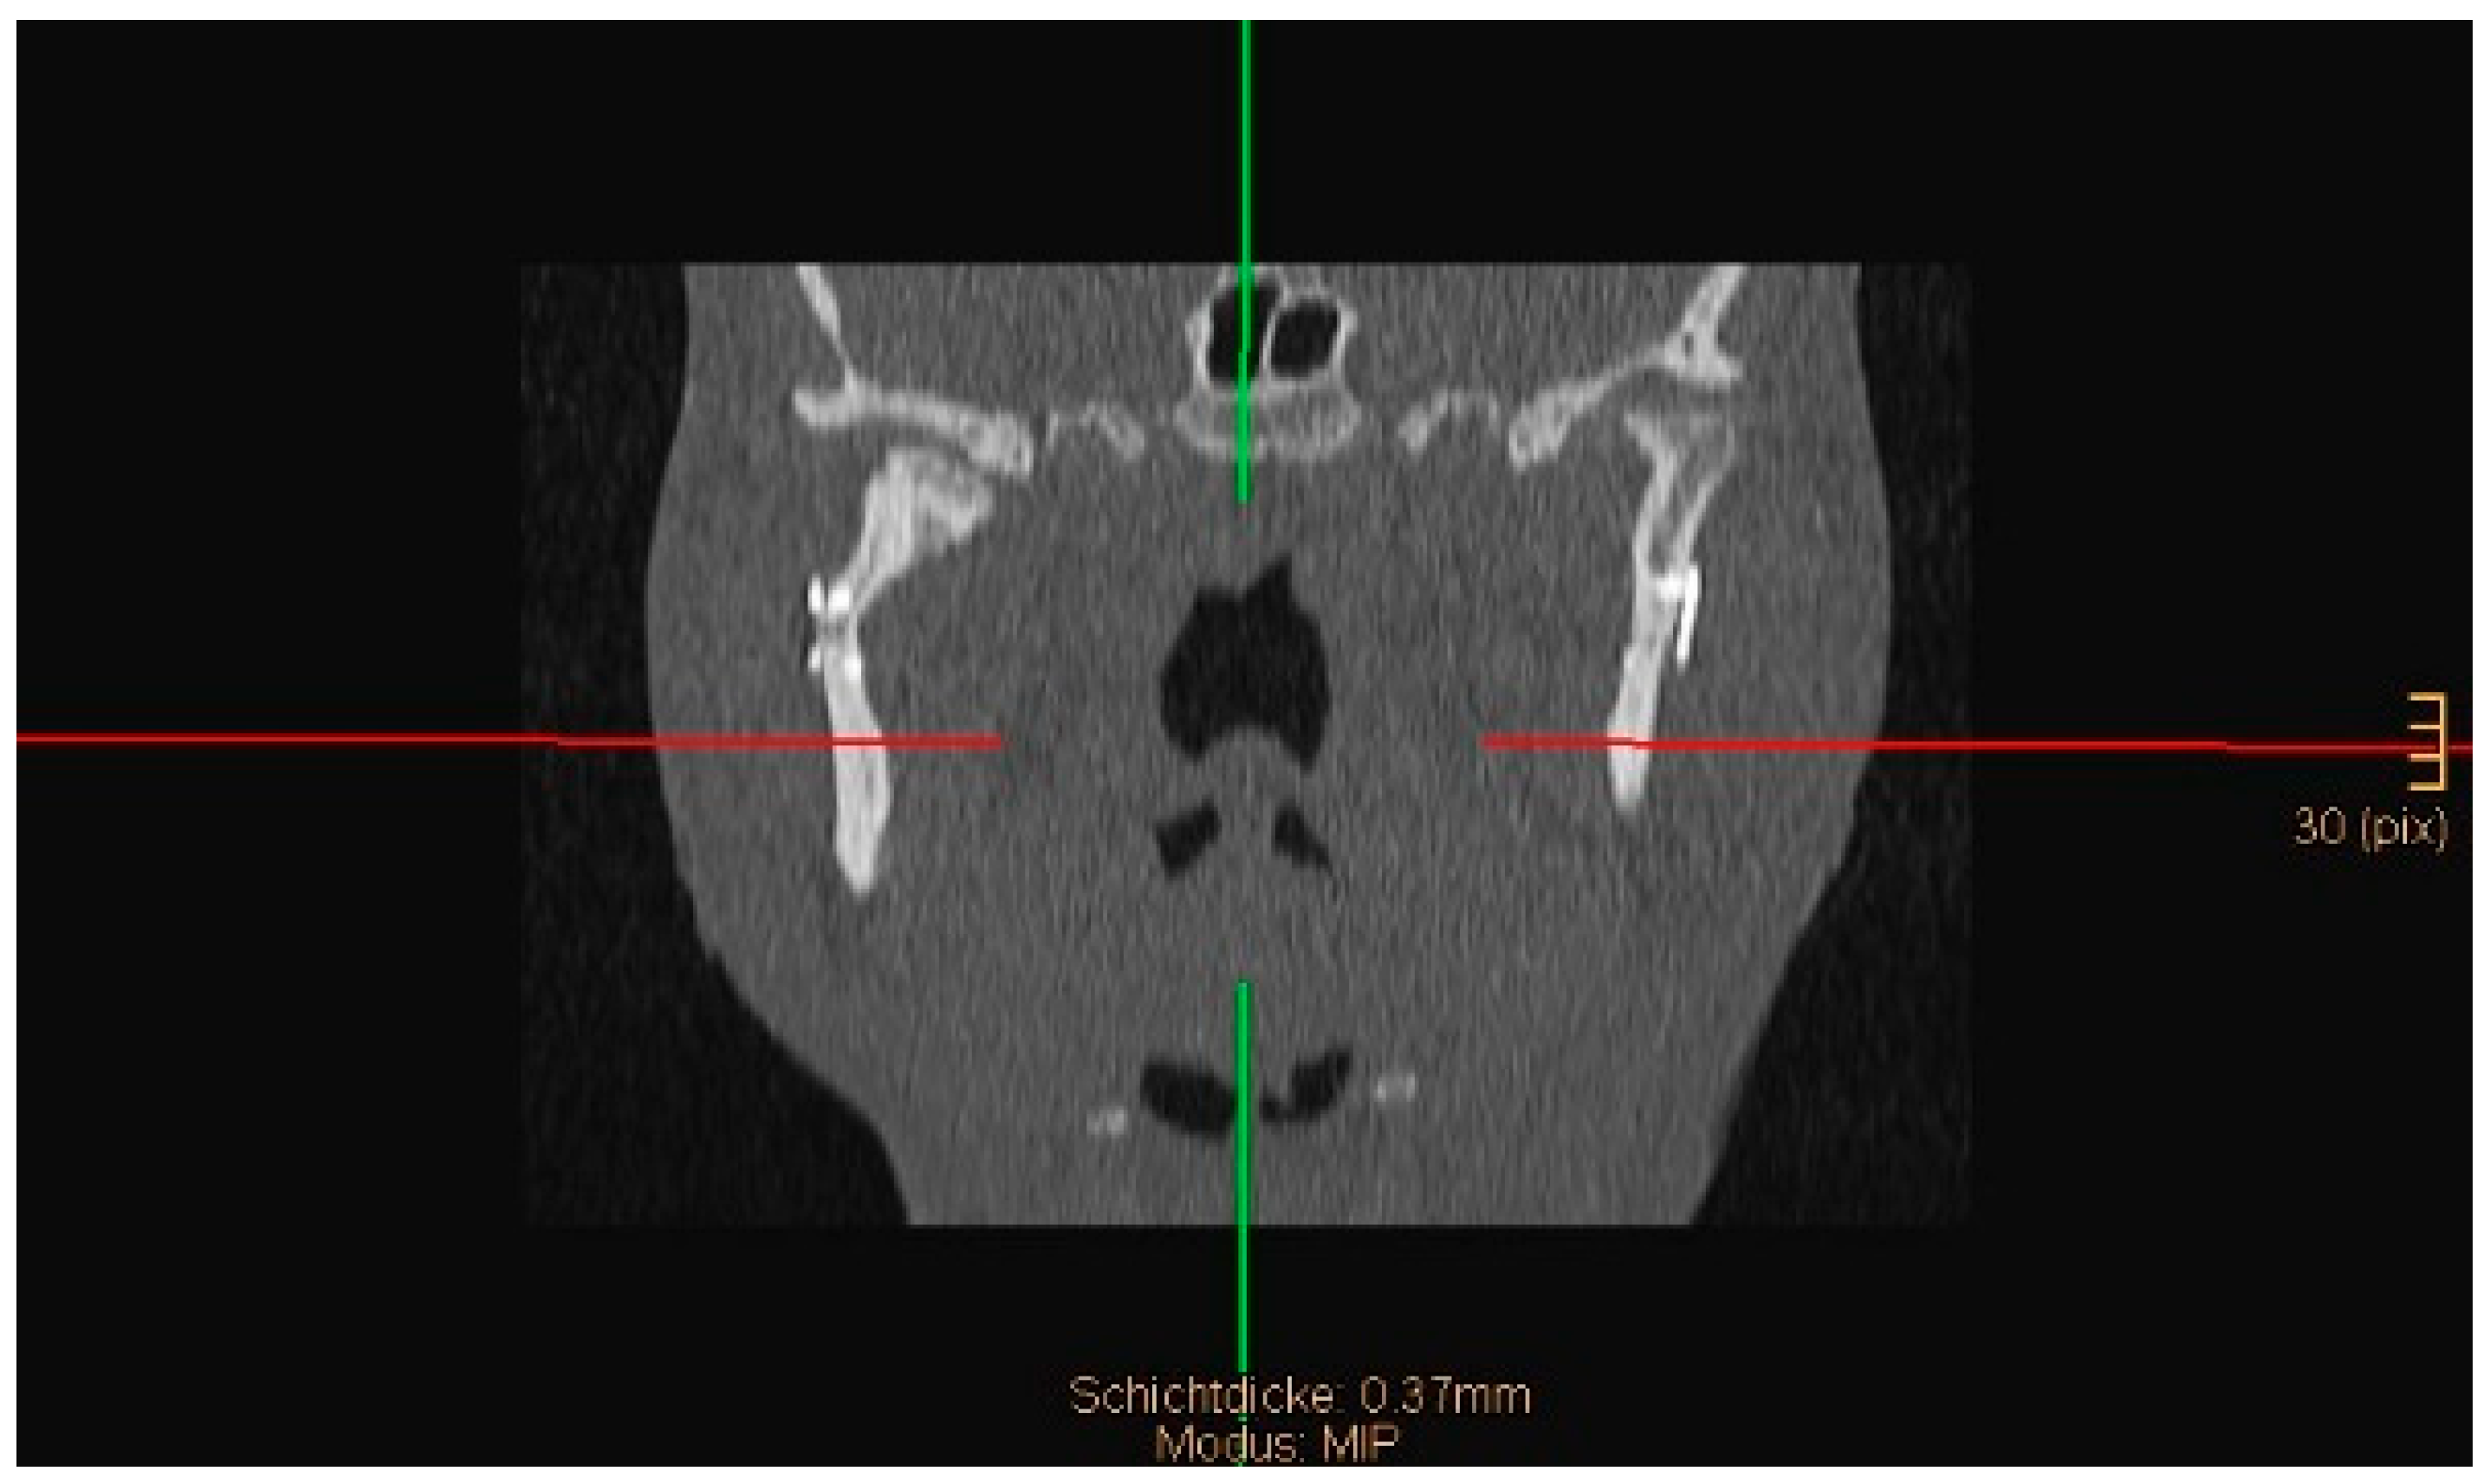

Figure 5. Coronal CT scan showing both condyles after ORIF. A widening of the mandible, caused by a small lingual gap that persisted even after lag screw osteosynthesis at the symphysis, resulted in an angulation of the condylar neck on the right-hand side (same patient as in Figure 3 and Figure 4). The image shown was taken on the third postoperative day after drainage removal and the situation did not worsen over time (last follow-up 1 year postop).

Two operations had to be redone because of inadequate reposition in the symphysis/parasymphysis with broad (>2 mm) lingual splay. In both cases, straight miniplates were removed. Osteosynthesis was achieved with lag screws. Figure 3 depicts plate osteosynthesis of a symphyseal fracture with a broad lingual gap (Figure 3). Figure 4 shows the same patient after redo operation and osteosynthesis of the same fracture with a lag-screw and a marked reduction in the lingual splaying (Figure 4). Figure 5 demonstrates the condylar reduction in the frontal plane in the same patient. Figure 6 and Figure 7 show the patient’s occlusion (Figure 5, Figure 6 and Figure 7). The third redo operation was due to nonunion and infection of an angular fracture with fracture of the two condylar plates. In this case, after removal of the infected miniplate, the angle fracture was stabilized with a reconstruction plate and a miniplate from an extraoral approach; the two broken miniplates at the condylar process were left in situ.